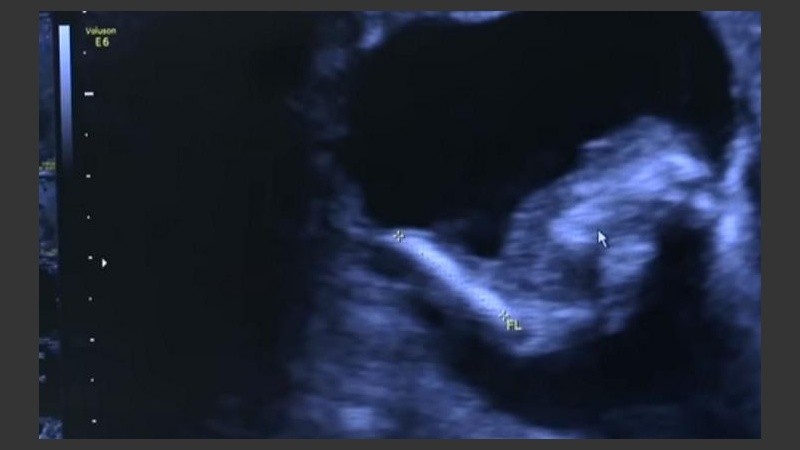

De acuerdo a lo que publicó el diario Página 12, durante su séptimo mes de embarazo, una mujer llamada Mónica Vega se realizó una ecografía de rutina en Barranquillas. Fue entonces que se detectó que dentro del feto que se estaba gestando en su vientre había otro feto, más pequeño pero con cordón umbilical y líquido amniótico.

La anomalía conocida como “fetus in fetu” se produce cuando las células no se separan en el momento indicado. Los gemelos dividen sus células en la primera semana de gestación y a partir de allí comienzan a formarse. Si ese proceso se da en la segunda semana se producen siameses y si es después del día 17 se llega al “fetus in fetu”.